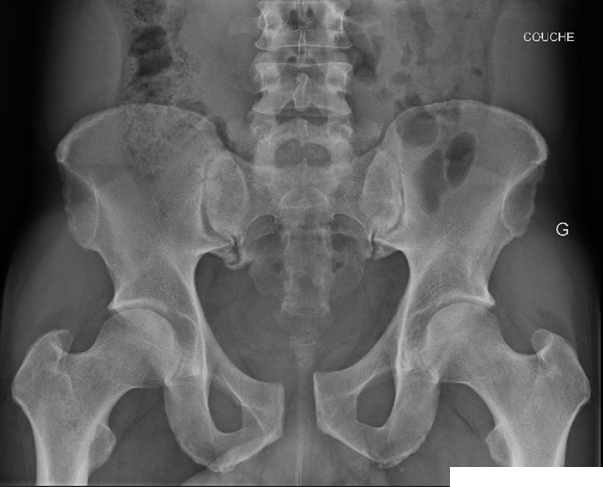

La radiographie du bassin de face révèle une fracture de type open book (« livre ouvert ») avec un élargissement de 22 mm au niveau de la symphyse pubienne :

Une ceinture pelvienne est rapidement mise en place. Le bilan d’extension par scanner injecté du bassin ne montre aucune lésion ligamentaire postérieure ni fracture associée, ni aucun signe de saignement actif mais un hématome des tissus mous adjacent à la symphyse pubienne. Le bilan sanguin ne révèle pas d’anémie ou trouble de la coagulation. Le patient est transféré au bloc opératoire pour une fixation chirurgicale du bassin.

Le degré de rotation externe, et donc l’ampleur de l’ouverture de la symphyse pubienne, détermine l’étendue des atteintes postérieures. En général, pour un diastasis pubien inférieur ou égal à 2,5 cm, les ligaments sacro-iliaques antérieurs restent intacts. Cependant, lorsque le diastasis dépasse 2,5 cm, les ligaments sacro-iliaques antérieurs sont fréquemment rompus, tandis que les ligaments sacro-iliaques postérieurs restent préservés, entraînant une instabilité horizontale.